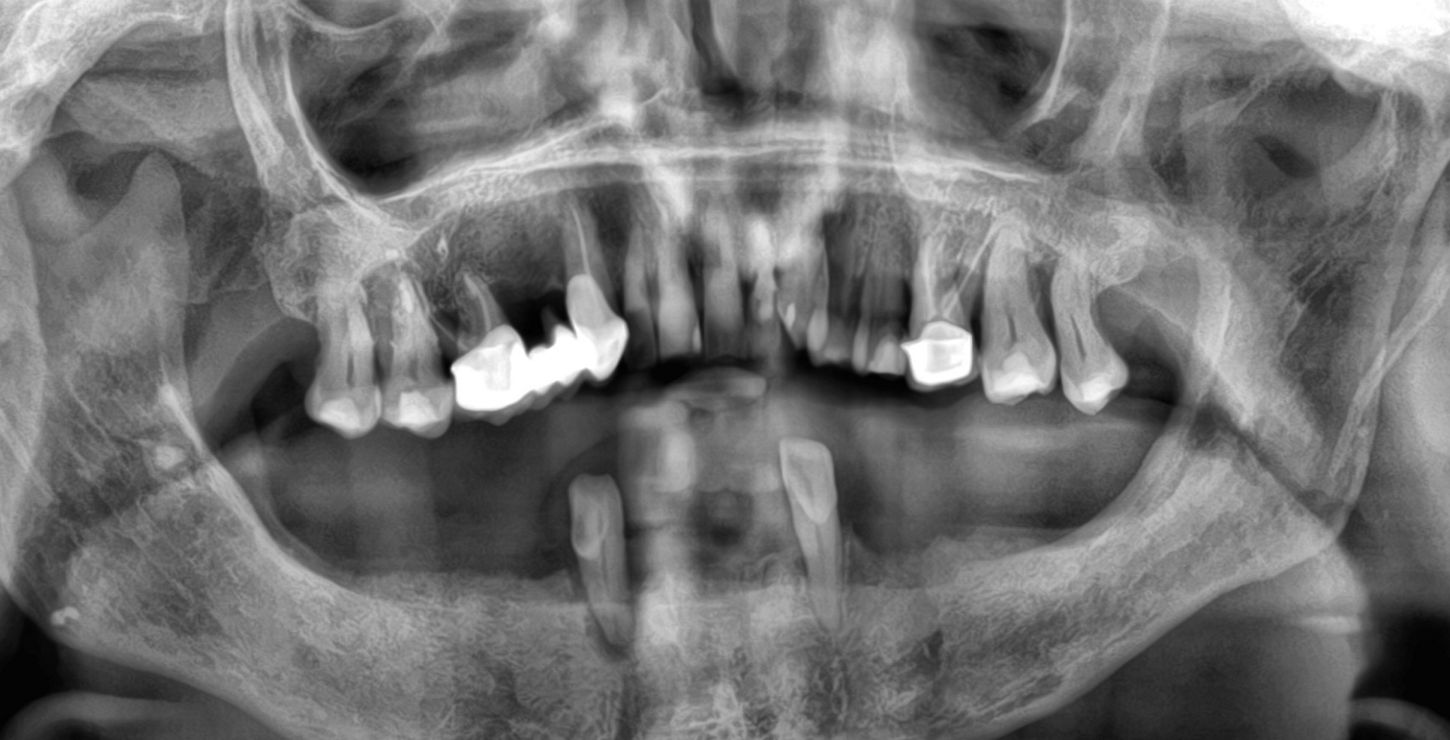

1a. 1b. Pre-operative panoramic X-ray and CBCT showing moderate generalised bone resorption in the mandible, a reduction in vertical dimension in the posterior region and the planned positioning of mini- implants.

1a

1b